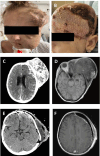

Background: Ewing sarcoma is a rare malignant neoplasm that is primarily localized in bone tissues. The prognosis for patients with a newly diagnosed localized Ewing sarcoma has been greatly improved by multimodality treatment. However, treating patients with disseminated or recurrent disease is challenging, with a 5-year overall survival rate of <30%. Case Report: A 17-year-old female with an asymptomatic tumor of the left temple underwent 3 cycles of vincristine, ifosfamide, doxorubicin, and etoposide and achieved partial remission. However, the patient refused further chemotherapy and surgical intervention and was lost to follow-up. After 7 months, the patient presented again with a sizeable tumor on her left temple and worsening symptoms. Chemotherapy with alternating cycles of vincristine, doxorubicin, cyclophosphamide, ifosfamide, and etoposide according to the EURO EWING 2012 trial was initiated. After a positive response, debulking surgery was performed, followed by postsurgical radiation, and partial remission was achieved. Conclusion: Optimal treatment protocols for recurrent Ewing sarcoma are lacking. Treatments are individualized based on the patient's response to treatment and the decisions of tumor boards. Patients with rare tumors such as Ewing sarcoma benefit from multidisciplinary collaboration, resulting in improved quality of care and treatment outcomes.